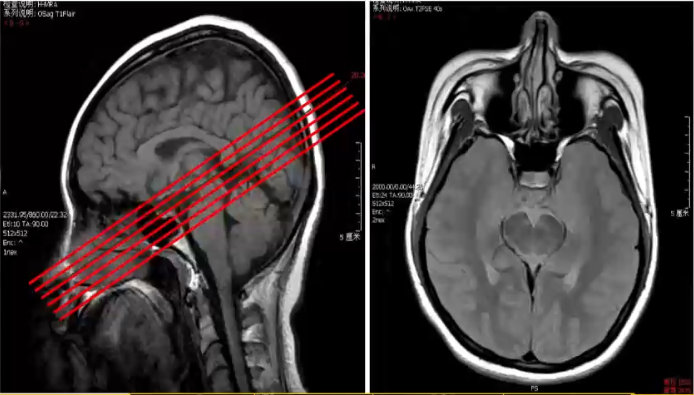

经蝶手术入路评价:切层平行于鼻蝶线,范围包括蝶窦和蝶鞍区

Hamberger的蝶窦分型

√甲介型:鞍前蝶窦发育小,窦壁与鞍底间硬化骨质>10mm。

√鞍前型:蝶窦腔后缘于A线前

√半鞍型:蝶窦腔后缘于AB线间

√全鞍型:蝶窦腔后缘于B线前

√鞍枕型:蝶窦腔后界越过B线达枕骨

√N线(Nasion线):鞍结节至后床突的连线

√A线:鞍结节垂直于N线

√B线:蝶鞍后床突垂直于N线